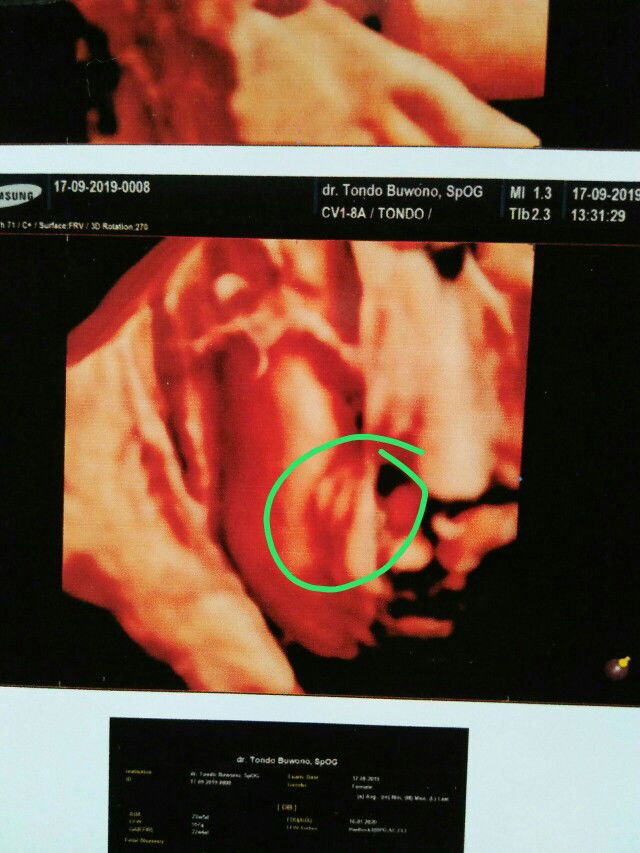

Bun ini benar usg cewek nggak bun???sharing dong bun yang pernah usg jenis kelamin dengan hasil cewek

usg

Itu jlas bgt ya bun cewe

Insyaallah cwe ya bun, kalo di usg cwe tingkat keakuratan 70% kalo di usg cowo akuratnya lebih tinggi 80%, itu yg aku tau dr dokter bun